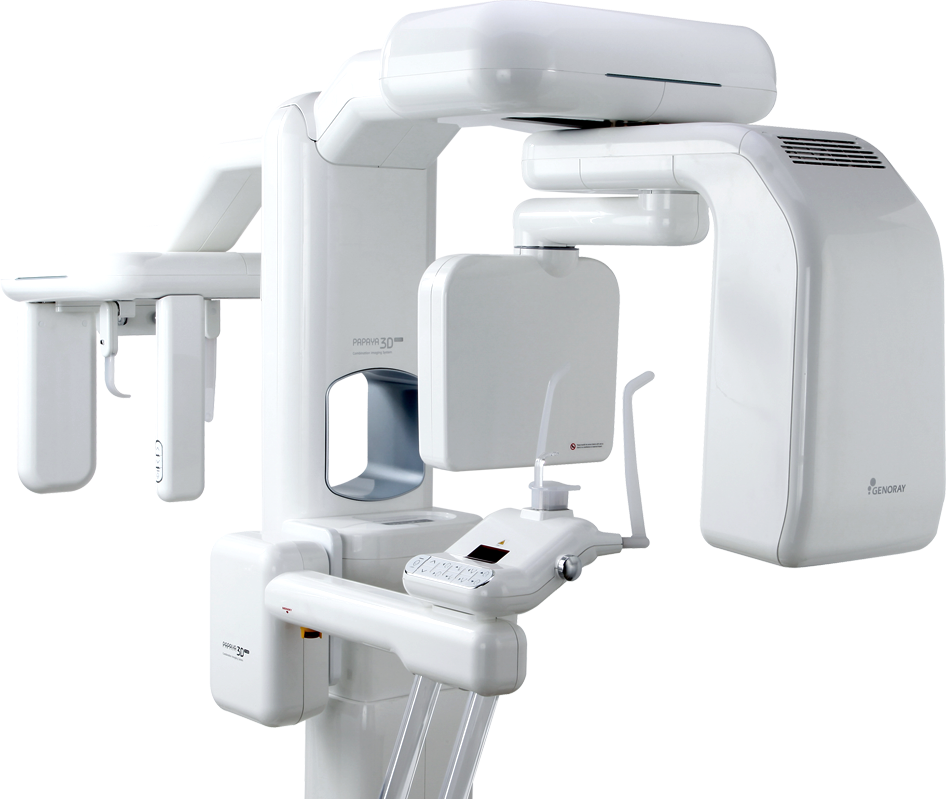

Превосходное качество изображения

Возможность выбора автоматических программ сканирования

Различные программы для каждого режима исследования, помогут обеспечить точную диагностику

Свободный выбор зон интереса

- Свободный выбор области сканирования и разрешения.

- Получайте оптимальные снимки с минимальным облучением

Ультра быстрая цефаломитрия

Максимально ускоренное время исследования, уменьшает артефакты при движении пациента и снижает лучевую нагрузку

Улучшенная обработка изображений SMARF™

(функция подавления рентгеноконтрастности)Умная система позиционирования

Автоматическая подстройка подбородочного упора, согласно выбранной зоне сканирования.

- Максимально ускоренное время исследования, уменьшает артефакты при движении пациента и снижает лучевую нагрузку